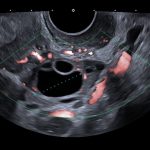

In women, chlamydia can spread to the womb, ovaries or fallopian tube causing pelvic inflammatory disease (PID).

PID can cause a number of serious problems, such as:

- Infertility

- Chronic pelvic pain

- Increased risk of ectopic pregnancy